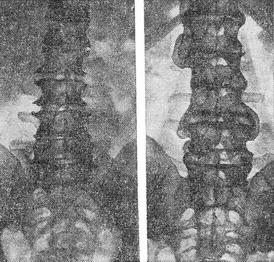

![]() Спондильоз (рентгенограми): зліва - загострення і кісткові виступи по краях тіл поперекових хребців; праворуч - з'єднання суміжних поперекових хребців масивними кістковими «дужками». Міжхребцеві диски збережені.  |

Рентгенологічне дослідження дозволяє встановити спондильоз, визначити поширеність і вираженість морфологічних змін. Рентгенограми хребта роблять у двох проекціях, щоб судити про стан всіх відділів тіл хребців. Основний рентгенологічний ознака спондильозу - остеофіти (див.) по краях тіл хребців, тобто звапнення зв'язок. Вони можуть бути у вигляді невеликих загострень, клювовидных виступів або масивних «дужок» (рис.), з'єднують тіла суміжних хребців.